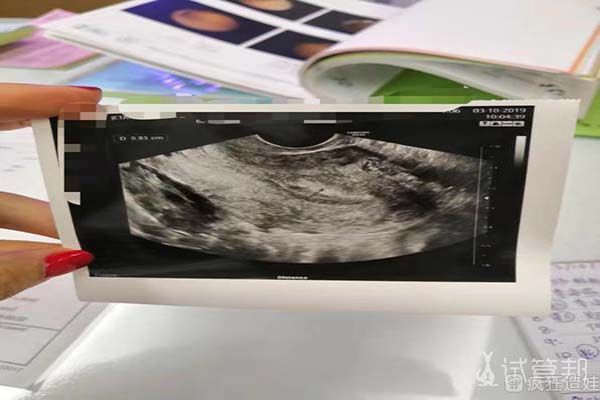

移植过程很简单,也很快。移植结束后我在医院休息了两个多小时。我是在第十二天的时候验孕的,结果很棒,一次就成功了。其实在第7天左右我就总感觉自己怀上了,感觉还是很奇妙的。